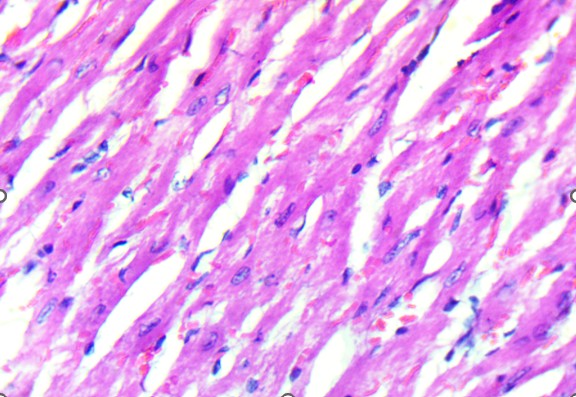

Histological analysis revealed that the heart was structurally preserved in all groups. In both control and treated animals, the cardiac tissue exhibited well-aligned myocardial fibers with distinct cross-striations and centrally located nuclei. No evidence of myocardial necrosis, interstitial edema, vascular congestion, or inflammatory infiltration was observed. Even in high-dose groups, the myocardium retained normal architecture, supporting the conclusion that the extract did not induce structural cardiotoxicity under these experimental conditions (Figure 2). In contrast, the lungs demonstrated a more apparent dose-dependent vulnerability to the extract. Control animals exhibited healthy pulmonary architecture, with well-expanded alveoli, thin interalveolar septa, and intact bronchiolar epithelium. These features were largely maintained in the low-dose group, although a few animals showed mild epithelial irregularities.

A. Control. . B. Treated

Figure 2. Heart of Swiss albino mice: (A) Control myocardium showing intact fibers with clear striations and central nuclei. (B) Treated myocardium displaying preserved architecture without necrosis, edema, or inflammatory infiltrates.

Histological examination of the heart revealed well-preserved myocardial architecture in both control and treated animals (Figure 2A–B). Myofibrils were regularly aligned, cross-striations were intact, and nuclei were centrally placed, findings consistent with the absence of cellular injury or inflammatory infiltration. Even at the highest extract dose, the myocardium exhibited no signs of necrosis, edema, or vascular compromise, indicating that D. stramonium did not induce structural cardiotoxicity under these experimental conditions. This aligns with clinical observations of Datura poisoning in humans, where tachycardia and arrhythmias are common yet typically reversible, reflecting autonomic dysregulation rather than direct myocardial damage (Krenzelok, 2010; Al Shaikh & Sablay, 2005).